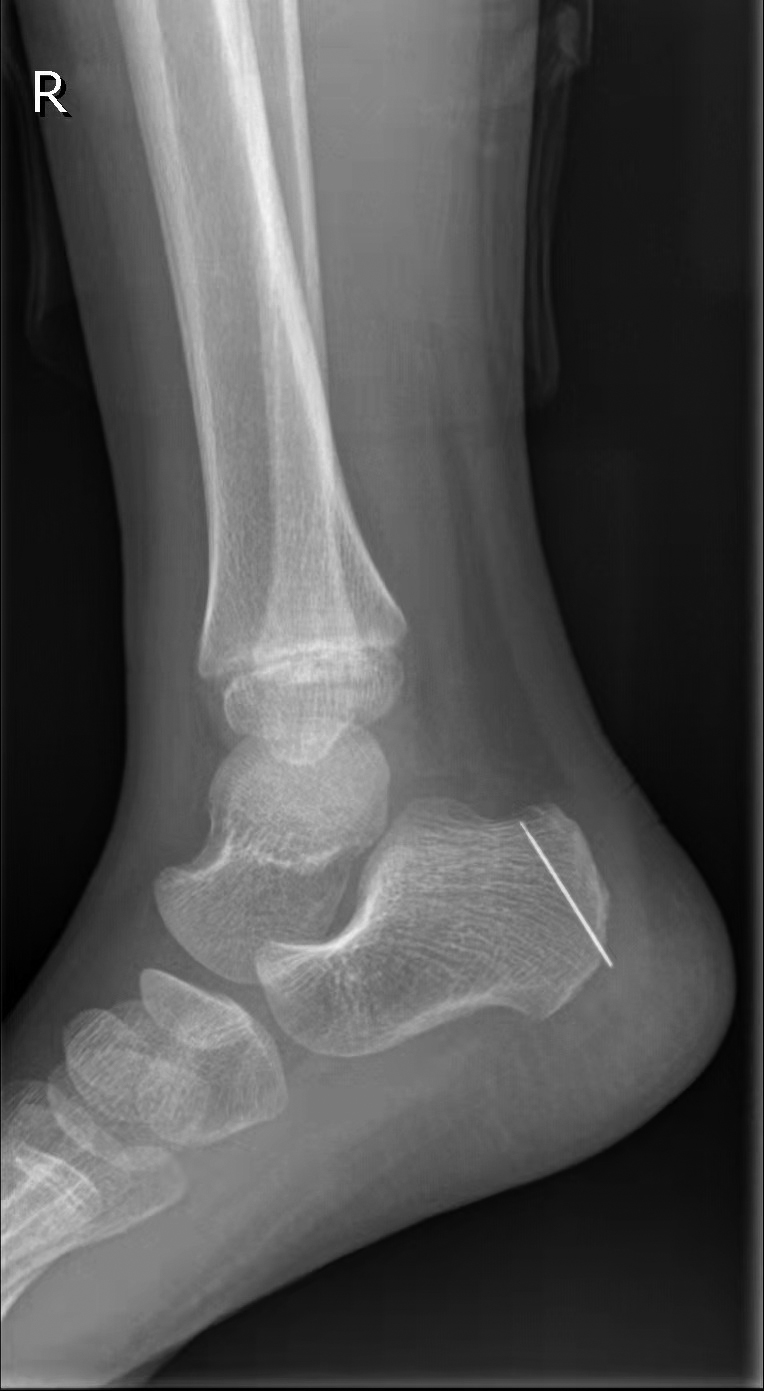

几天前,小杨在爷爷家玩,小杨在床上蹦蹦跳跳时不小心踩到了绣花针,绣花针扎进了右脚踝,当时没什么疼痛的感觉。第二天,小杨妈妈带着他去公园玩了一天。到了第三天,小杨的脚踝开始出现红肿的迹象,妈妈带他去温州市中心医院检查。该院骨科副主任医师楚宇鹏经过检查,发现脚踝处有一个肉眼很难发现的细小针孔,安排其去拍片。片子出来后,着实让小杨妈妈吓了一条,一枚绣花针“藏”在脚踝里。

楚宇鹏说,看似简单的体内金属异物取出有时像“大海捞针”,因为这枚绣花针在体内会游走,需要先将绣花针定位,通过多次拍片找到准确位置再进行手术。医生用了整整一个小时才将绣花针从小杨的右脚踝处取出。